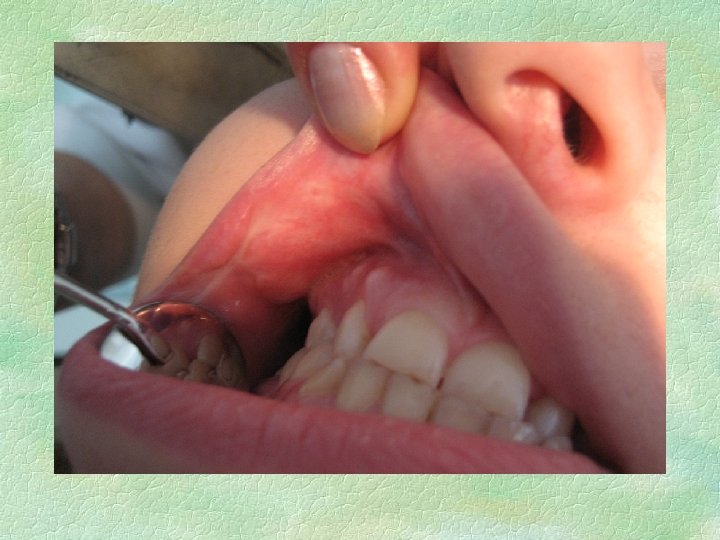

Хронический рецидивирующий афтозный стоматит (ХРАС) . § Больной Н. , 22 года. § Клинический диагноз: ХРАС, фибринозная форма. Третий день после возникновения.

ХРАС, фибринозная форма.